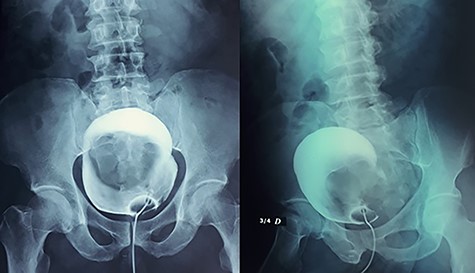

A hydatic cyst was suspected but hydatic serology was done twice and was negative. We completed in the first place by a urethrocystography on which we notice the presence of a 12-cm mass projecting on the bladder area (Fig. 2). And to better and further characterize this cystic formation, a pelvic magnetic resonance imaging (MRI) was performed, concluding the presence of a 13 × 10 cm supra-rectal and retro-vesical multilocular cystic formation of heterogeneous signal, with the presence of liquid level in some loci, having a T1 hypersignal (Fig. 3) and T2 hypo signal evoking a hematic content having a thin wall increasing after injection of gadolinium, the whole evoking either a hemorrhagic cystic retro-peritoneal mesothelioma or cystic lymphangioma.

Presence of a 12-cm mass projecting on the bladder area in the cystography.